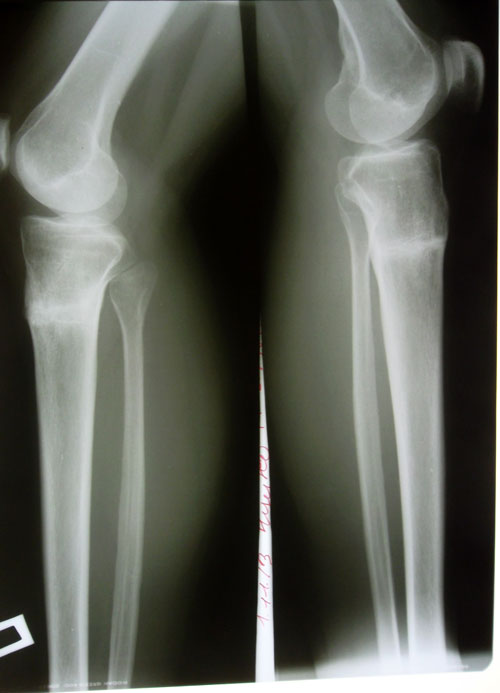

- Диагноз: О-образная деформация ног

Господи, неужели это мои ножки?! Не верится, не устану говорить СПАСИБО Вам большое!Sekretar Onipko писал(а):Через 5 месяцев после снятия аппаратов!